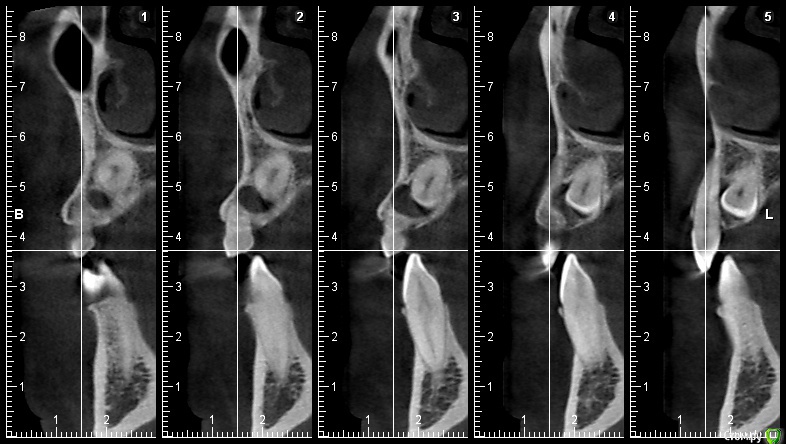

natalie_summerwhile Опубликовано 10 июля, 2017 Автор Поделиться Опубликовано 10 июля, 2017 Во рту вместо клыка молочный Ссылка на комментарий